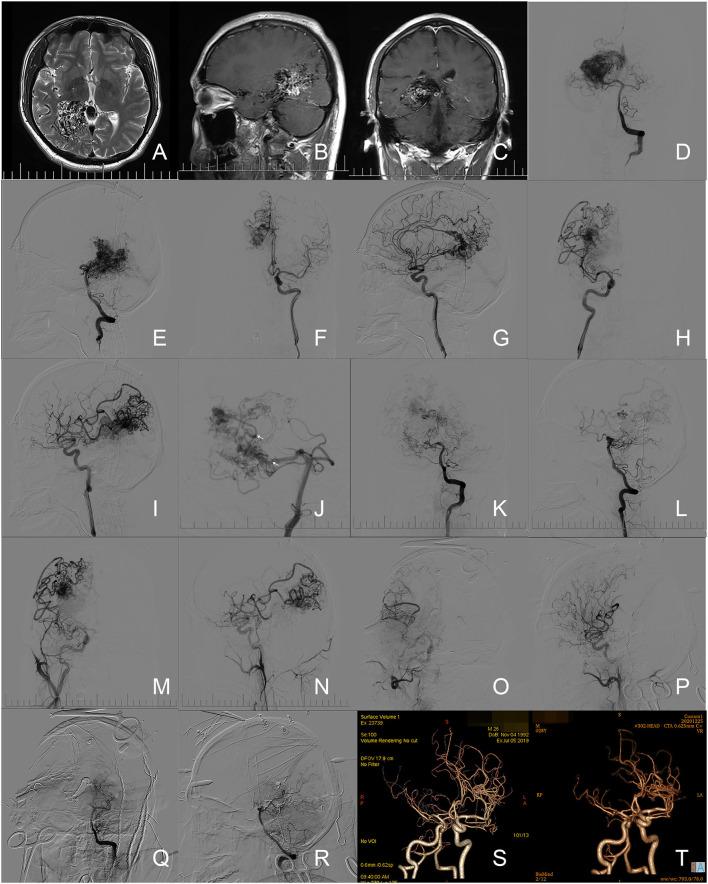

It remains a challenge in surgical treatments of brain arteriovenous malformations (AVMs) in Spetzler-Martin Grade (SMG) IV and V to achieve both optimal neurological outcomes and complete obliteration. The authors reported a series of patients with AVMs in SMG IV and V who underwent a surgical paradigm of endovascular embolization and simultaneous microsurgical resection based on the one-staged hybrid operation. Participants in the multicenter prospective clinical trial (NCT03774017) between January 2016 and December 2019 were enrolled. Patients who received endovascular embolization plus microsurgical resection (EE+MRS) and those who received intraoperative digital subtraction angiography plus microsurgical resection (iDSA+MRS) were divided into two groups. Information on clinical features, operative details, and clinical outcomes were extracted from the database. Deterioration of neurological deficits (DNDs) was defined as the primary outcome, which represented neurological outcomes. The time of microsurgical operation and blood loss were defined as the secondary outcomes representing microsurgical risks and difficulties. Outcomes and technical details were compared between groups. Thirty-eight cases (male: female = 23:15) were enrolled, with 24 cases in the EE+MRS group and 14 in the iDSA+MRS group. Five cases (13.2%) were in SMG V and 33 cases (86.8%) were in SMG IV. Fourteen cases (36.8%) underwent the paradigm of microsurgical resection plus intraoperative DSA. Twenty-four cases (63.2%, = 24) underwent the paradigm of endovascular embolization plus simultaneous microsurgical resection. Degradations of SMG were achieved in 15 cases. Of the cases, two cases got the residual nidus detected via intraoperative DSA and resected. Deterioration of neurological deficits occurred in 23.7% of cases ( = 9) when discharged, and in 13.5, 13.5, 8.1% of cases at the follow-ups of 3, 6, and 12 months, respectively, without significant difference between groups ( > 0.05). Intracranial hemorrhagic complications were reported in three cases (7.9%) of the EE+MRS group only. The embolization did not significantly affect the surgical time and intraoperative blood loss. The subtotal embolization or the degradation of size by 2 points resulted in no DNDs. The paradigms based on the one-staged hybrid operation were practical and effective in treating high-grade AVMs. Appropriate intraoperative embolization could help decrease operative risks and difficulties and improve neurological outcomes.

在Spetzler-Martin分级(SMG)IV级和V级脑动静脉畸形(AVM)的外科治疗中,实现最佳神经学预后和完全闭塞仍然是一项挑战。作者报告了一系列SMG IV级和V级AVM患者,他们接受了基于一期杂交手术的血管内栓塞联合显微手术切除的手术模式。纳入了2016年1月至2019年12月期间多中心前瞻性临床试验(NCT03774017)的参与者。接受血管内栓塞加显微手术切除(EE+MRS)的患者和接受术中数字减影血管造影加显微手术切除(iDSA+MRS)的患者被分为两组。从数据库中提取临床特征、手术细节和临床结果的信息。神经功能缺损恶化(DND)被定义为主要结局,代表神经学预后。显微手术时间和失血量被定义为代表显微手术风险和难度的次要结局。比较两组的结局和技术细节。共纳入38例患者(男∶女=23∶15),EE+MRS组24例,iDSA+MRS组14例。5例(13.2%)为SMG V级,33例(86.8%)为SMG IV级。14例(36.8%)患者接受了显微手术切除加术中DSA的模式。24例(63.2%,n=24)患者接受了血管内栓塞联合显微手术切除的模式。15例患者实现了SMG降级。其中,2例患者通过术中DSA检测到残留病灶并进行了切除。出院时23.7%(n=9)的患者出现神经功能缺损恶化,在术后3、6和12个月的随访中,分别有13.5%、13.5%和8.1%的患者出现神经功能缺损恶化,两组之间无显著差异(P>0.05)。仅EE+MRS组有3例(7.9%)患者报告了颅内出血并发症。栓塞对手术时间和术中失血量无显著影响。次全栓塞或体积缩小2级未导致DND。基于一期杂交手术的模式在治疗高级别AVM方面切实有效。适当的术中栓塞有助于降低手术风险和难度,并改善神经学预后。